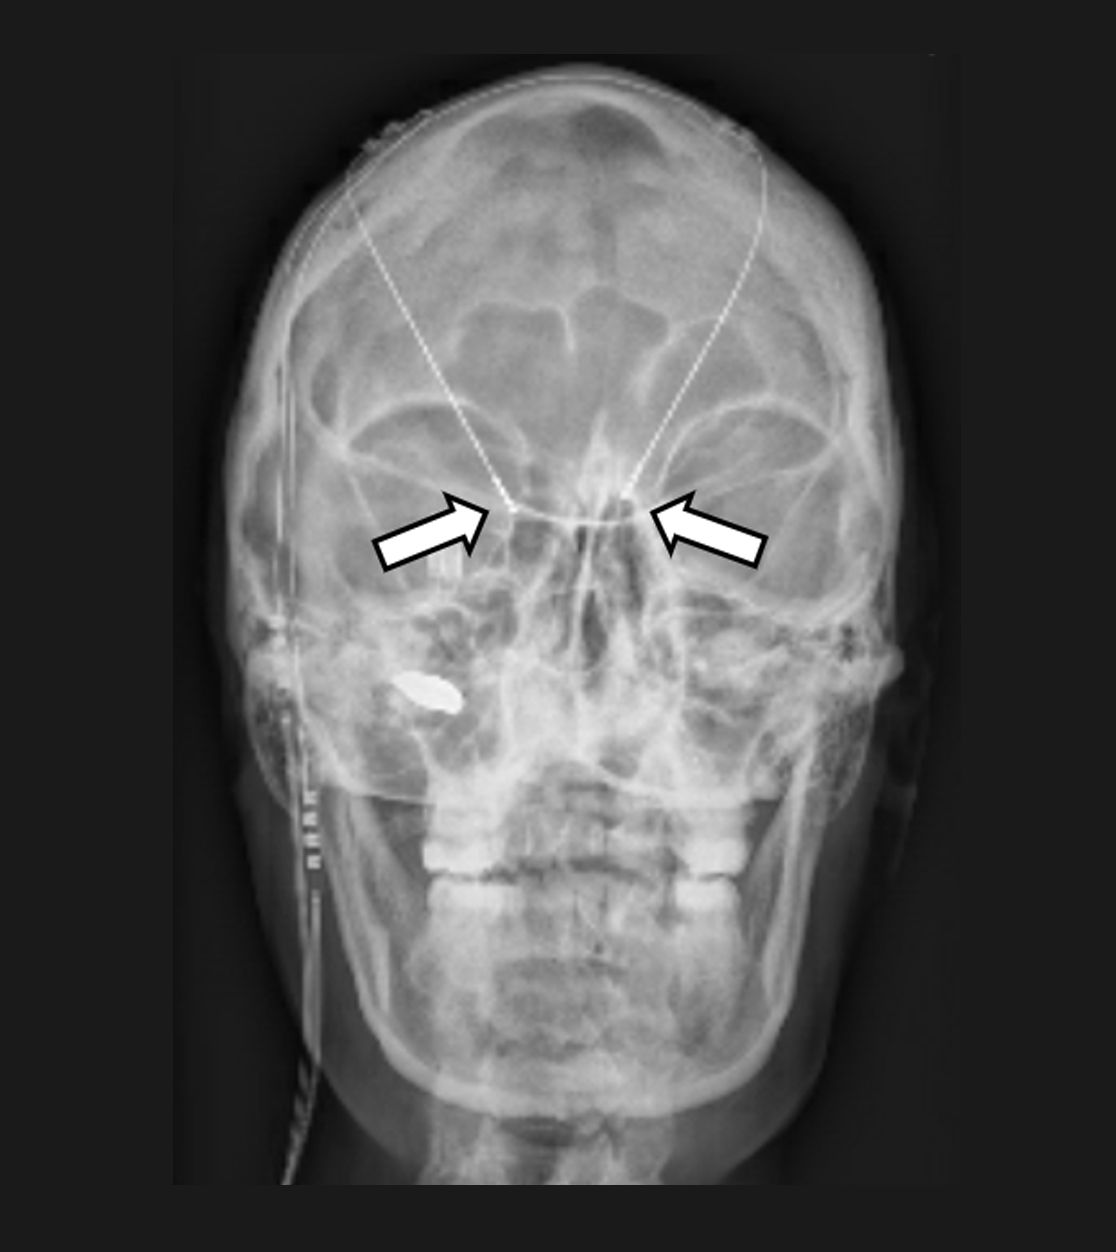

In das Gehirn implantierte Elektroden zur Tiefen Hirnstimulation (Pfeile)

Die Tiefe Hirnstimulation, welche meist für Patienten mit Bewegungsstörungen wie Parkinson oder einer Dystonie eingesetzt wird, kann auch bei Patienten mit chronischen Gesichtsschmerzen oder einem sog. zentralen Schmerz zur Anwendung kommen. Es werden Elektroden gezielt mittels sog. stereotaktischer und robotischer Verfahren in kleine Kerngebiete des Gehirns implantiert und – wie bei anderen neuromodulativen Verfahren – an einen Impulsgeber (vergleichbar mit einem Herzschrittmacher) angeschlossen. Durch die Abgabe angepasster elektrischer Impulse sollen dann die Schmerzen gelindert und somit die Lebensqualität der Patienten verbessert werden. Wie bei der Motorcortexstimulation muss die Möglichkeit einer Tiefenhirnstimulation zur Schmerztherapie stets individuell evaluiert werden.